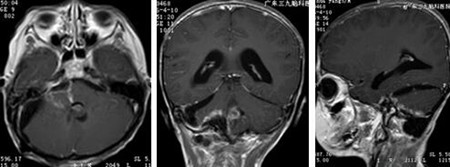

入院后完善术前检查,排除手术禁忌症后,杨宝应主任及其团队为薛仔实施“右侧桥小脑角区及上段脊髓右旁、四脑室内室管膜瘤切除术”,在显微镜下次全切除肿瘤,术后薛仔的症状明显好转,并辅以放化疗。

▲术后